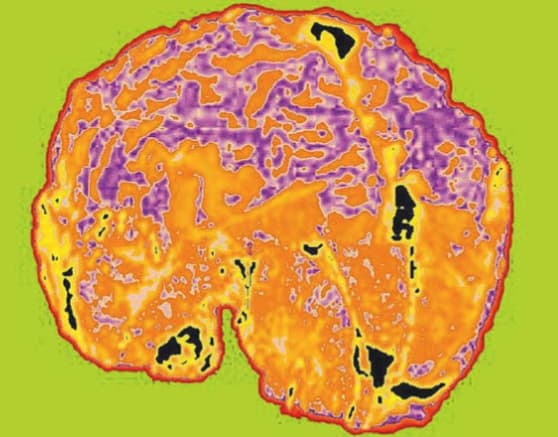

With U.S. Food and Drug Administration clearance, BMI will sell its Med-Seg imaging system with the 2-D version of the RHSEG software, licensed from NASA in 2002 and featured in Spinoff 2004. The device is intended to analyze medical imagery from computed tomography (CT or CAT) scans, positron emission tomography (PET) scans, magnetic resonance imaging (MRI), ultrasound, digitized X-rays, digitized mammographies, dental Xrays, soft tissue analyses, and moving object analyses; the technology is also equipped to evaluate soft-tissue slides such as Pap smears for the diagnoses and management of diseases. The advanced image segmentations produced by the RHSEG software allow the Med-Seg system to bring out details in these tests not previously seen with the naked eye. This allows for quick and accurate diagnosis of diseases. Additionally, unlike some other image-analysis devices, Med-Seg does not manipulate the image, so what the physician sees is truly what is there, providing truer images than many other imaging techniques.

The Med-Seg system reveals image properties not seen with even up-to-date image enhancement techniques. It is available with a custom data-mining server; a computational engine; and an object-oriented database to manage data, models, and results, and access BMI's Hierarchical Image Segmentation Beowulf Cluster, an online problemsolving network.

By extending the software's capabilities to three dimensions, BMI's device may be able to produce a pixellevel view of all sides of a tumor or lesion. While current technology can produce 3-D imagery, the RHSEG software will be able to segment an image in ways that more clearly define problem areas. For example, the 3-D version of Med-Seg may be able to identify very early buildup of soft plaque within the arteries or identify density levels of microcalcification in mammographies, allowing physicians to diagnose malignant breast tumors well before they would normally be seen. In brain images, the physicians using Med-Seg will also be able to make earlier diagnoses of tumors or arteriovenous malformations.